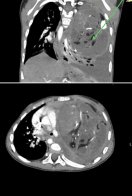

Медики вирішили розпочати хіміотерапію за життєвими показами — у максимально обережному, модифікованому режимі. Рівень онкомаркера почав стрімко знижуватися, стан дитини поступово стабілізувався. Після цього лікарі провели надскладне оперативне втручання. “Ми дуже боялися, що Аня може не перенести операцію, настільки важким був її стан”, — згадує мама дівчинки.

Пухлину вдалося повністю видалити та усунути здавлення органів і відновити їх нормальне положення. Після операції маленька Аня продовжила хіміотерапію, щоб мінімізувати ризик рецидиву. Врешті контрольні обстеження, зокрема ПЕТ-КТ у грудні, показали, що ознак активного онкологічного процесу не виявлено.